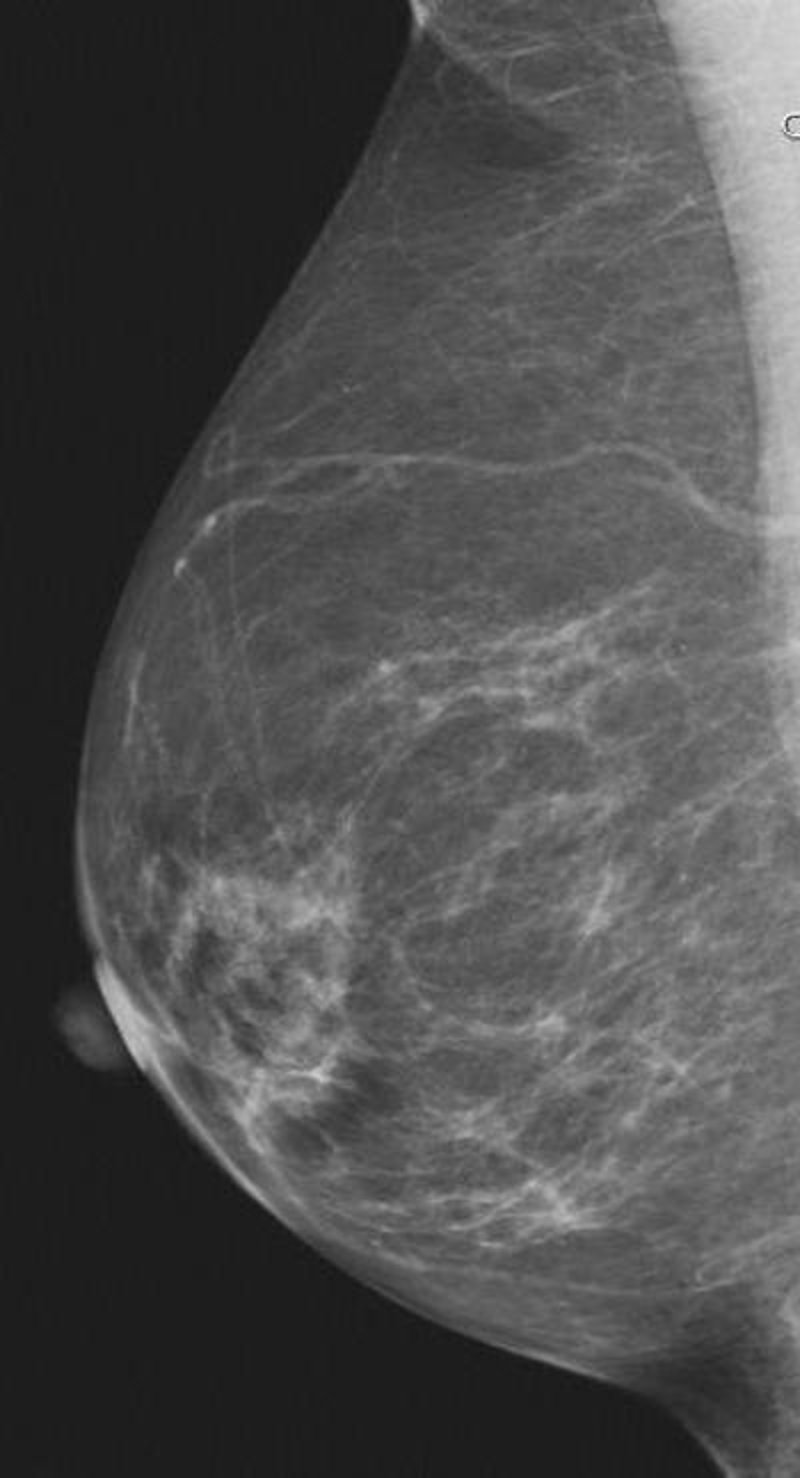

Mama, pecho

Foto: RADIOLOGICAL SOCIETY OF NORTH AMERICA